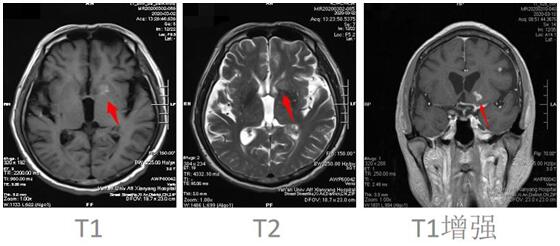

患者邱某,男,67歲 ,因“反復低熱頭痛40余天”入住我院神經(jīng)內(nèi)科三病區(qū),入院后行神經(jīng)系統(tǒng)體格檢查示:表情淡漠,腦膜刺激征陽性;行顱腦磁共振增強掃描示:顱內(nèi)可見多發(fā)點狀及小片狀結節(jié)灶,增強掃描呈小片狀及環(huán)形明顯強化,考慮①感染性病變,結核性腦膜炎可能,②轉移瘤待排:請結合臨床實驗室檢查;行腰椎穿刺術示:顱內(nèi)壓310mmH2O,潘氏試驗陽性,并于腦脊液中檢測出結核分枝桿菌(咸陽市首例)。腦脊液常規(guī):淡黃色清亮,白細胞計數(shù) 210*106/L,潘氏試驗陽性,中性粒細胞比率 90.0%。腦脊液生化:葡萄糖 1.40mmoI/L,氯 105.5mmol/L,微量總蛋白 2749mg/L,陳萍主任醫(yī)師、代昌飛副主任醫(yī)師及科室其他醫(yī)師慎重討論后考慮:結核性腦膜炎,并立即制定抗結核、降低顱內(nèi)壓、抑制腦水腫、減輕炎癥反應等相關治療方案。王寶艷護士長指導護理應加強護理,早期康復。經(jīng)討論匯總,為該患者制定特色治療方案,動態(tài)調(diào)整,密切觀察。在科室醫(yī)生護士的精誠協(xié)作下,患者渡過險關。復查腰椎穿刺術:初壓:170mmH20,常規(guī):潘氏試驗陽性;白細胞計數(shù) 120*106/L。淋巴細胞百分率 10.0%,中性粒細胞百分率 90.0%。生化:微量總蛋白 1503mg/L。出院后繼續(xù)抗結核治療。